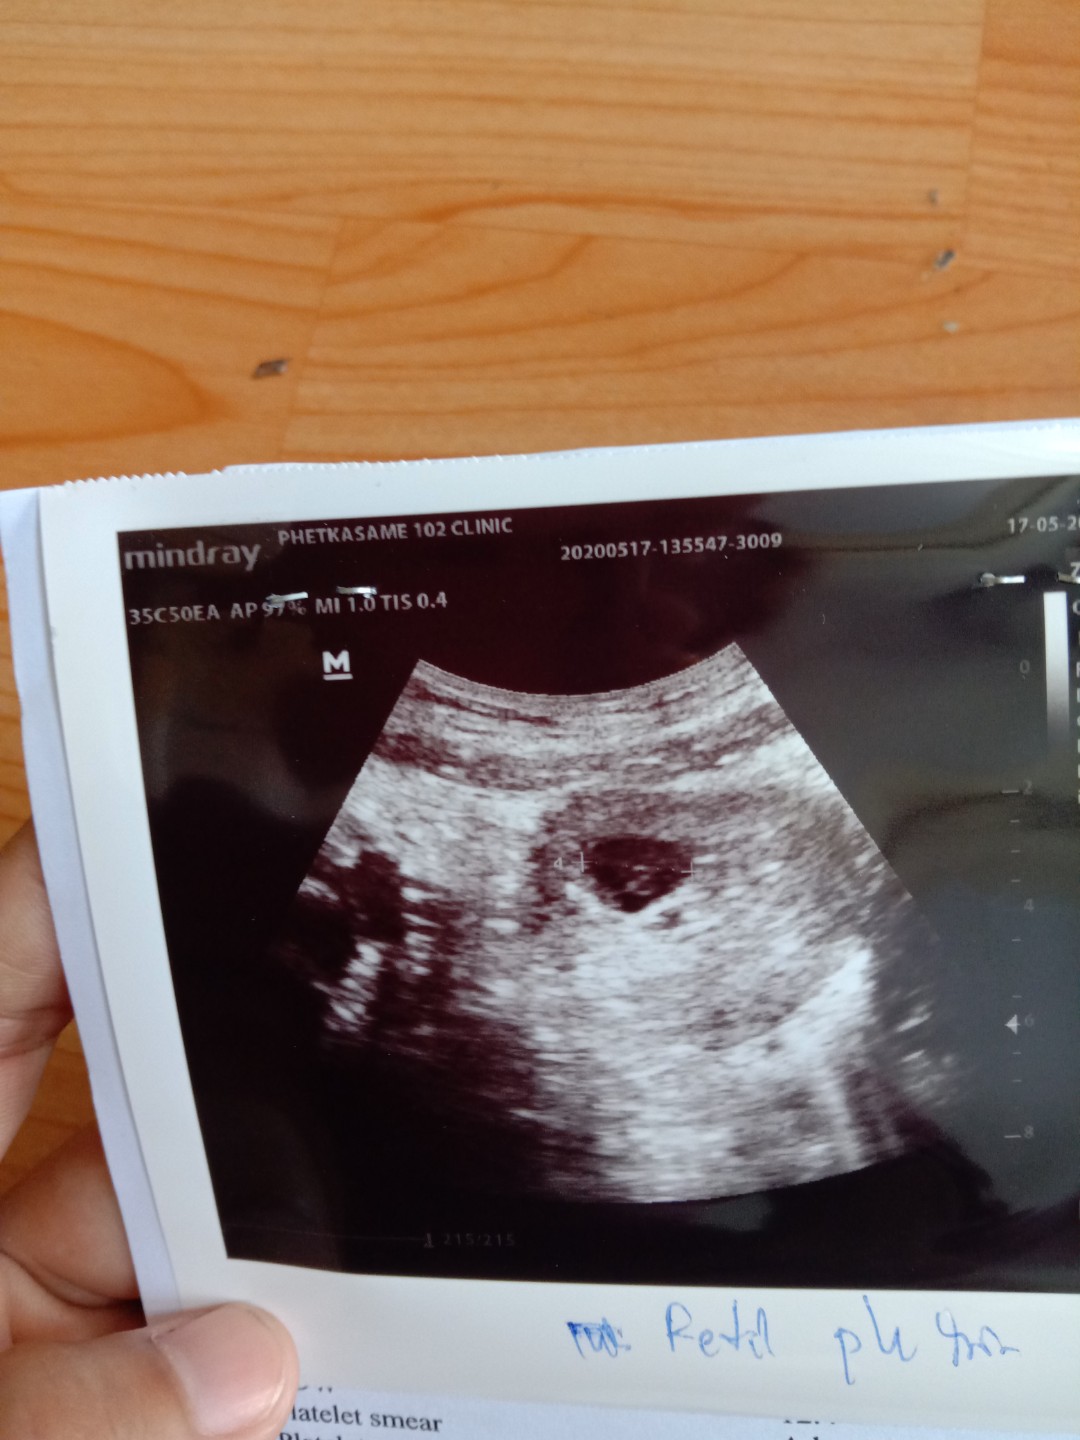

ท้อง 6 วีค

6 วีค แร้วแต่ยังไม่เจอเดกเรย แม่คนไหน 6 วีค ยังไม่เจอบ้างค่ะ ตอน 6 วีค (กังวลกลัวจะเปนท้องลมอะค่ะ)

บ้านนี้6วีค ซาวน์ผ่านหน้าท้องก็ยังไม่เห็นตัวอ่อนค่ะ ต้องรอ7วีค หมอนัดไปอีกรอบค่ะ

ของเราก็เหมือนกะนค่ะวันนี้ไปซาวก็ไม่เห็นเห็นแต่ถุงตั้งครรกังวลเหมือนกันค่ะ

ปกติคะ ตอนฝากครรภ์ 6 wks ไม่เจอเหมือนกันคะ ถ้าเจอแสดงว่าอายุครรภ์มากกว่านี้คะ